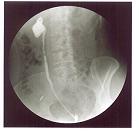

역행성신우조영술은 방광경을 사용하여 요관 입구로 가느다란 튜브(카테터)를 삽입하고 이 카테터를 통해 조영제를 주입하면서 사진을 촬영하는 검사법입니다.

이 검사는 경정맥신우조영술로는 충분히 조영되지 않은 부위나 충만 결손이 명확하지 않을 때 사용할 수 있는 매우 진단 가치가 높은 검사법입니다. 튜브 삽입 시 좌우의 요관에서 직접 소변을 채취하여 요세포 검사도 할 수 있습니다.

[ 역행성신우조영술 ]